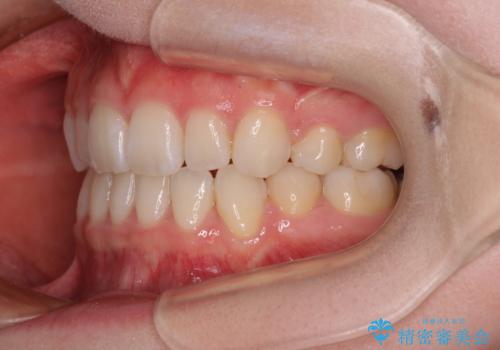

- 前歯の出っ歯と口元の閉じにくさを気にして来院された患者様です。

口元を積極的に引っ込めるために、上下左右の小臼歯4本を抜歯することとしました。

4本の歯を抜歯したことで、飛び出していた口元が引っ込み、横顔が大きく改善されました。